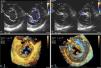

Caso clínicoUm homem de 52 anos é proposto para cirurgia valvular por regurgitação mitral severa secundária a fenda mitral e regurgitação aórtica moderada em válvula aórtica bicúspide. O ecocardiograma transesofágico 2D (ETE‐2D) mostrou uma junção AV comum, com uma válvula AV esquerda composta por três folhetos: um mural, um ântero‐superior e um póstero‐inferior com uma «fenda» orientada ao septo interventricular, na sua zona de aposição (Figura 1A‐B). Os músculos papilares estavam deslocados lateralmente, posicionando‐se junto das comissuras do folheto mural com as bridging leaflets. O exame 3D (ETE‐3D) permitiu detalhar as características anatómicas (Figura 1C‐D). De notar que não se evidenciou comunicação interauricolar ou interventricular, características dos DSAV.

A,B – 2D janela transgástrica. Em diástole (A), observa‐se o aspeto trifoliado do componente esquerdo da válvula AV e a «fenda» (*). Em sístole (B), evidencia‐se a regurgitação mitral com ponto de partida na «fenda».

Fig. 1C,D – 3D zoom em tempo real cropped images. Em diástole, por vista auricular (C) e ventricular (D), a morfologia dos três folhetos da válvula AV esquerda aparece bem detalhada e a orientação septal (ventrículo direito) da «fenda» bem definida. A presença de cordas anormais ligando os bordos da «fenda» ao septo interventricular é bem observada por vista ventricular (seta).

Aprecie‐se o formato elíptico do anel e a reduzida dimensão do folheto mural, outras particularidades de uma válvula esquerda AV. 1 – folheto ântero‐superior, 2 – folheto póstero‐inferior, 3 – folheto mural. AOV – válvula aórtica; LVOT – trato de saída do ventrículo esquerdo, TV – válvula tricúspide.